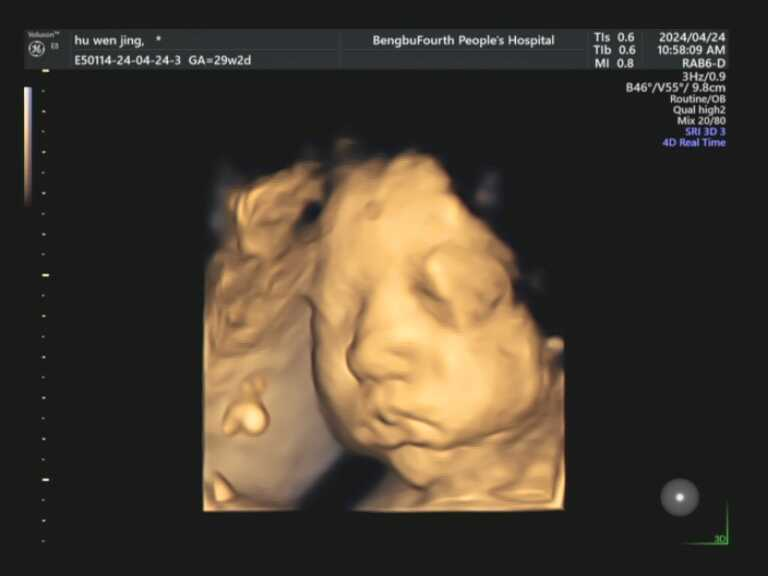

让我们赴一场与宝宝的

“初见”之约!

胎儿四维彩超

定格生命最初的感动!

在这里,您将看到宝宝在子宫里打哈欠、吮手指、微笑、伸懒腰的可爱瞬间。在这里,您将获得宝宝人生中第一段动态“写真”和“照片”,成为您家庭最珍贵的回忆。